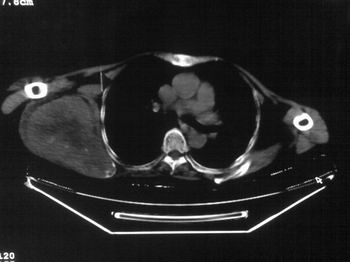

以下是引用zhangxu5888在2007-9-11 16:25:00的发言:[br]有侧肩胛骨溶骨性破坏且见软组织成分,增强软组织强化明显,中央见低密度坏死区!根据病史10年,考虑良性肿瘤恶性变!性质待定!

以下是引用老爱克斯新网客在2007-9-11 18:22:00的发言:[br]应该是良性肿瘤恶变,但因晚期破坏严重不能见到原来肿瘤征象无法判断,